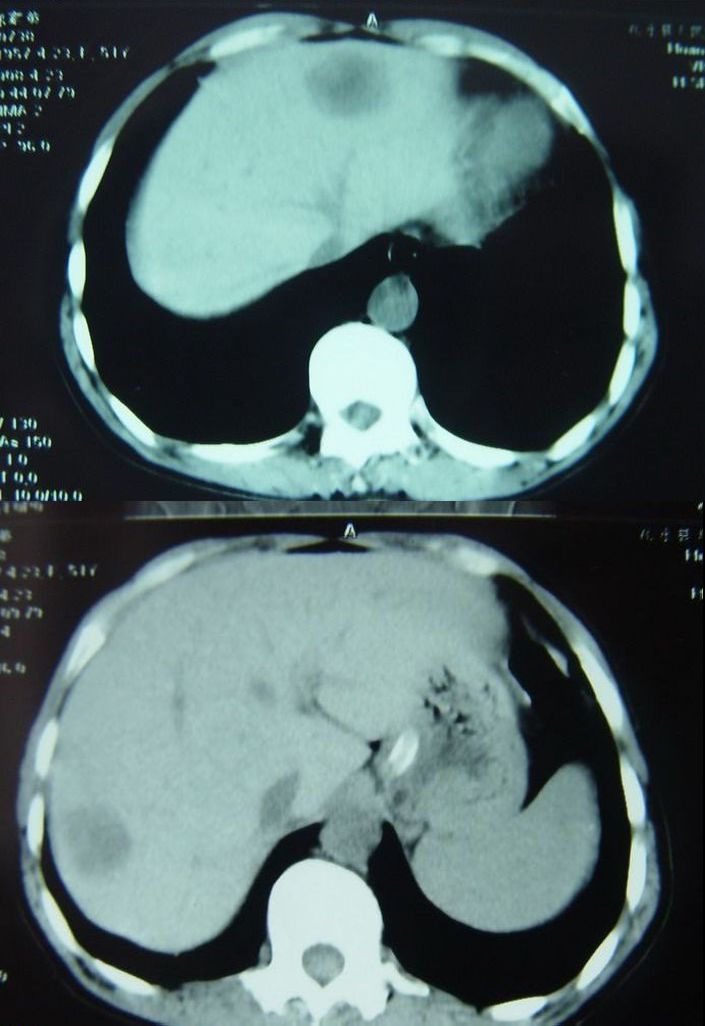

为了引起战友们的注意,我特意把典型的几个层面发表在这里,上两个是平扫,病灶密度较低,边缘较清楚,增强分别是动脉期,门脉期,延迟后4分钟和7分钟后的图片,讨论一下看,到底是什么性质的病变?

肝转移瘤也可出现类似肝血管瘤ct增强表现,既然升结肠ca可定,那么本例肝脏改变肝转移瘤首选,建议mri检查。

本例的困惑是延迟后强化更明显

我不是高手,不过我认为本例的牛眼征还是较典型的,所以考虑为转移。

支持肝脏多发转移瘤,(体现了肝动脉及门静脉双重供血之特点)

本人个子不高,我考虑肝左叶为血管瘤,肝右后叶为转移瘤。

牛眼征;边缘环壮强化;象转移瘤

转移瘤动脉期不会出现边缘结节状血管样强化,延迟扫描血管瘤和转移瘤都可以出现环状显著强化,二者病灶中心都可以出现坏死。故动脉期为主要鉴别依据。若再行延迟扫描(15分钟后)对二者的鉴别应该也有帮助。我认为是典型的血管瘤。

肝脏血管瘤可能性大,增强早期明显呈结节状强化,而延时扫描呈环状强化,但有可能延时不够或中间有坏死区.